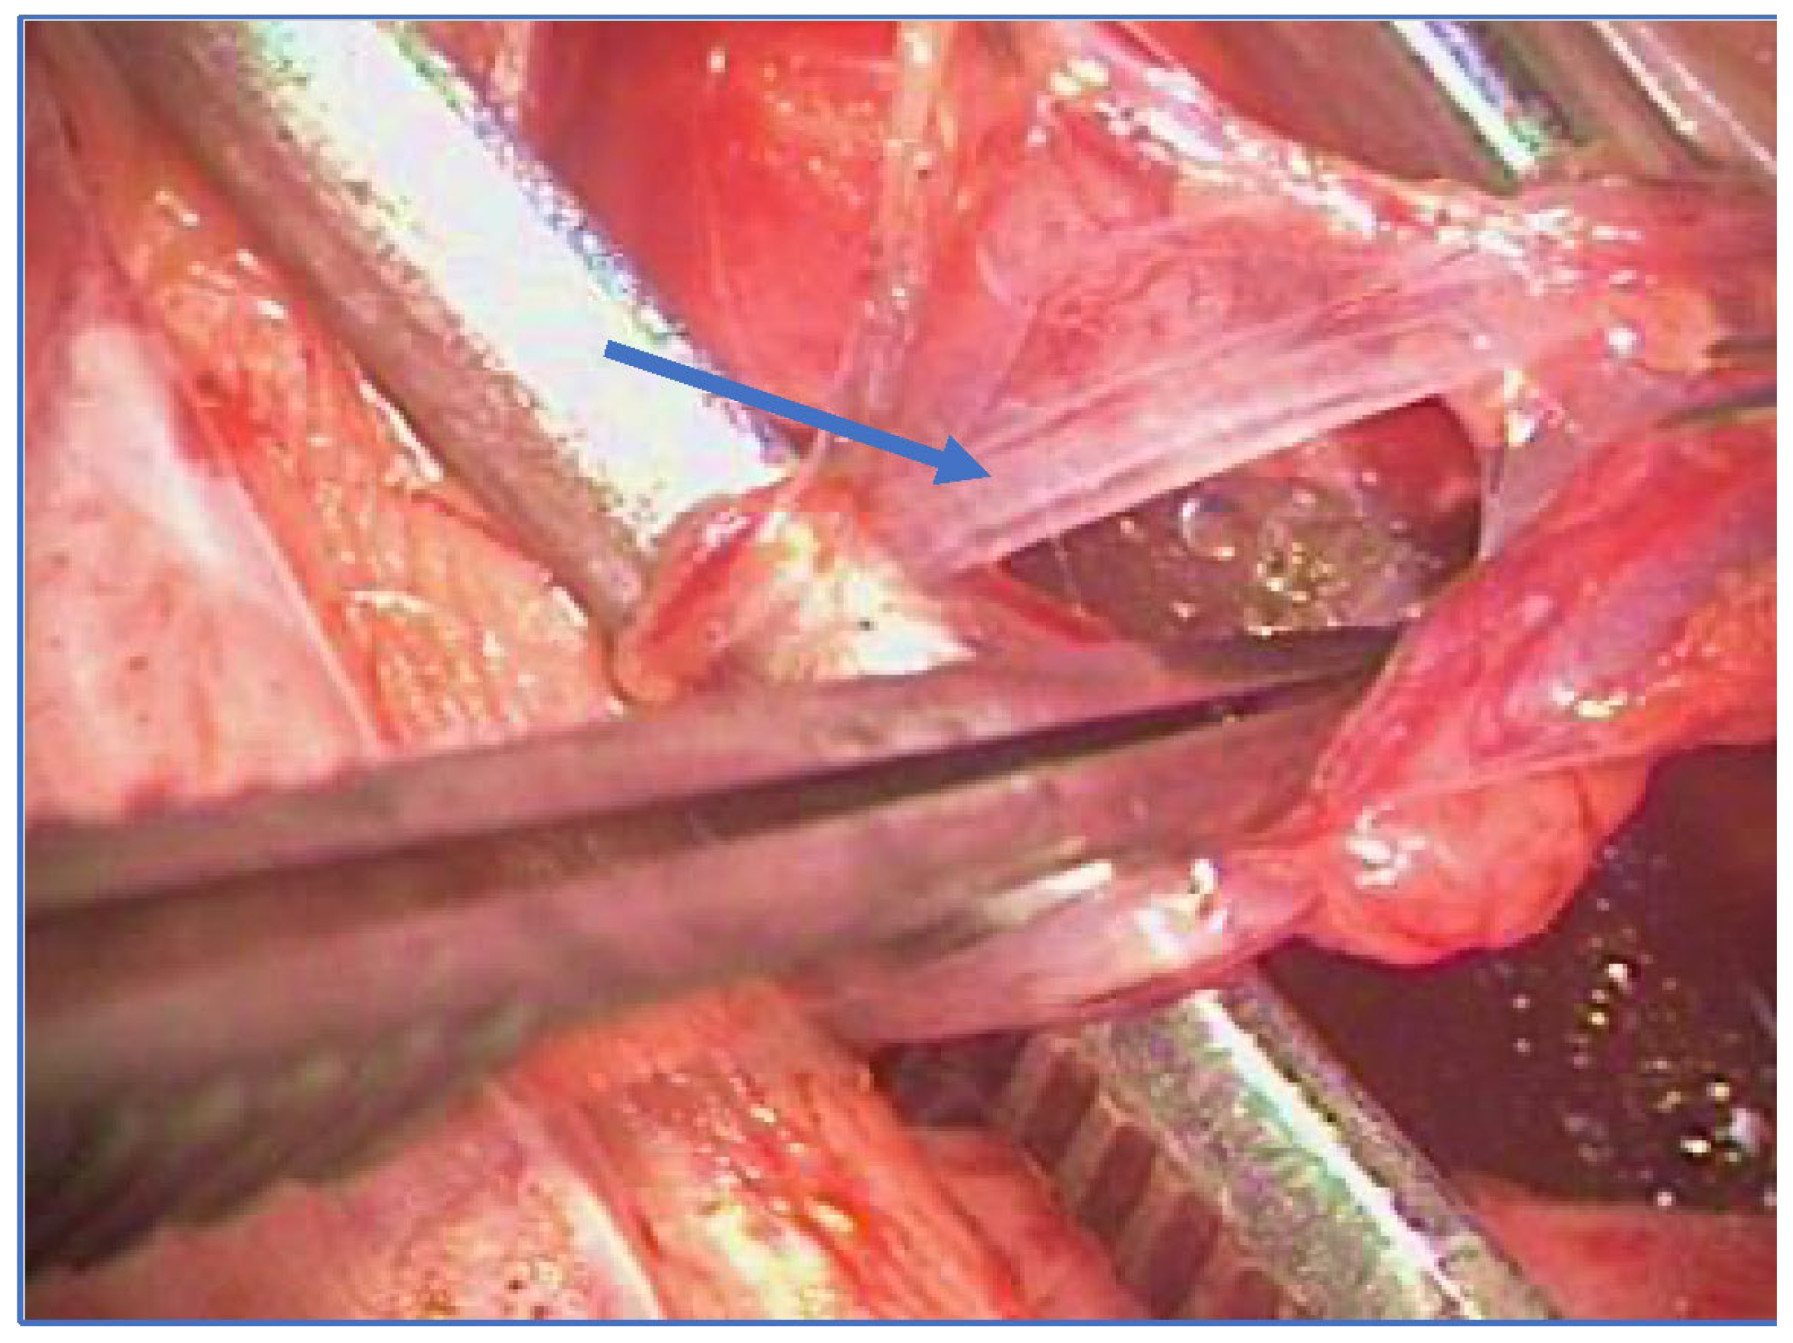

A recent Palomo technique variant consists of sparing a few lymphatic vessels with the aid of an operating microscope, to avoid post-operative hydrocele which might occur after the standard Palomo procedure [17][18][19][20]. The approach is moved from the sub-inguinal to the pre-peritoneal level, just above the internal inguinal ring, as described by Jones for nonpalpable testes [21]. The internal spermatic veins are reached by splitting the muscle plane and thus preserving the integrity of the inguinal channel. The deferential vein can be evaluated but not necessarily ligated, considering that dilation is not synonymous with reflux [17] (Figure 1).

Figure 1. Microsurgical lymphatic sparing Palomo technique (arrow: spared lymphatics).